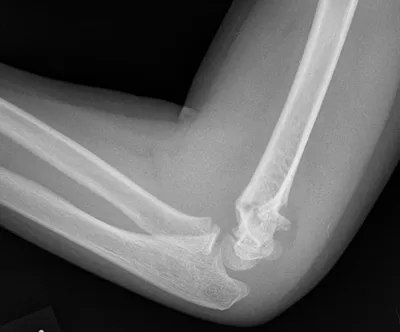

Supracondylar fracture of elbow

Elbow

4/10/2026